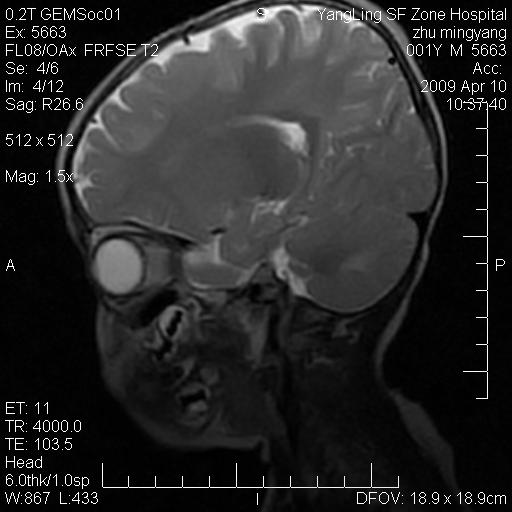

患者:1岁半,两天前外伤收住我院,ct检查小脑占位

考虑星形细胞瘤,建议增强

髓母细胞瘤或血管母细胞瘤,增强后可以鉴别;影像资料见 <。鱼博浪老师的《中枢神经系统ct与mr鉴别诊断》 小脑部肿瘤章节。

髓母细胞瘤或血管母细胞瘤!支持!

支持考虑髓母细胞瘤

考虑----髓母细胞瘤可能性大

考虑髓母细胞瘤或室管膜瘤。

支持髓母细胞瘤。

考虑髓母细胞瘤。

考虑髓母细胞瘤或星形细胞瘤

考虑髓母细胞瘤.

考虑髓母细胞瘤可能性大。

小脑肿瘤.考虑髓母细胞瘤可能.

就病灶部位及临床资料首先考虑髓母.